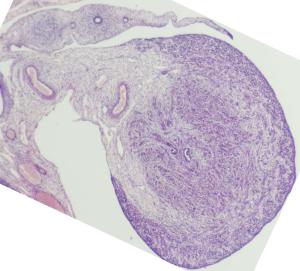

Stage

Stage:

CfS

Day:

d6